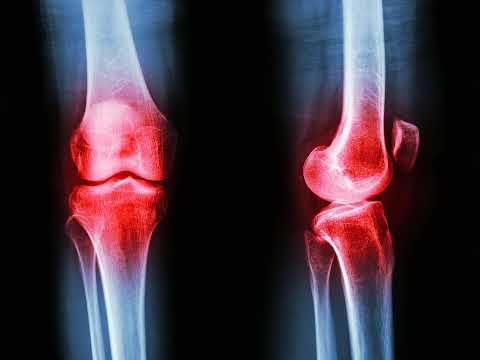

Недавнє дослідження, опубліковане в журналі Engineering, виявило перспективну нову терапевтичну мету для лікування ревматоїдного артриту (РА). Дослідники встановили, що природна сполука, обакулактон (OL), може пом’якшувати перебіг хвороби не шляхом широкого придушення імунної системи, а за рахунок виправлення метаболічного дисбалансу у процесах переробки жирів організмом.

На ревматоїдний артрит страждає приблизно 1% населення планети, що становить мільйони людей, які стикаються з хронічним болем і потенційною інвалідністю. Сучасна терапія часто не забезпечує повну ремісію або супроводжується важкими побічними ефектами.